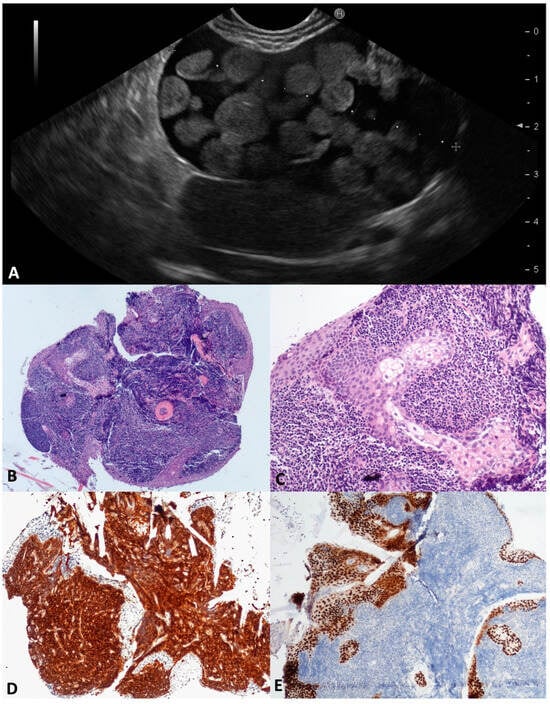

3.4. Cystic Lymphangioma (CL)

Pancreatic CLs are extremely uncommon (0.2% of PCLs), affecting typically young women; their growth is positively influenced by hormones (contraceptive, pregnancy, hyperprogesteronemia). Probably due to the progressive dilation of lymphatic vessels caused by insufficient drainage [], CLs usually present as large and well-defined multicystic lesions with a thin septa, and less frequently have a unilocular or oligocystic appearance (Figure 5A). The intracystic viscous fluid seems chilous in the FNA, due to the triglycerides content [,] (Figure 5B). In our series, four middle-aged patients (three males) presented with a large cyst (mean size 60 mm) at different locations within the pancreas. In two out of four (50.0%) patients, no definitive characteristics of CLs were preoperatively found, either in the fluid cytology or TTNB specimens, and the diagnosis was reached after surgery. According to the microscopy, the two TTNB diagnostic specimens were composed of smooth muscle bundles and collagenous fibers interposed between slit-like vascular spaces lined by a flat endothelium; the D2-40 and CD31 immunolabelling was positive. Focally, small aggregates of lymphocytes were identified in the collagenous tissue (Figure 5C–F).

Figure 5.

Cystic lymphangioma. Endoscopic ultrasound revealed an irregularly shaped multilocular cyst close to the pancreatic parenchyma, with a thin wall and septa (A). The aspirated fluid appeared as thick “milky” white-yellowish fluid (B). Numerous narrow lymphatic vessels lined by a cuboidal epithelium were separated by bundles of smooth muscle with few aggregates of lymphocytes (C). Immunolabelling for endothelial markers D2-40 (D) and CD31 (E). Bundles of smooth muscle actin (SMA) positive cells (F). Hematoxylin–eosin original magnification ×100 (C); D2-40 original magnification ×200 (D); CD31 original magnification ×200 (E); SMA original magnification ×200 (F).